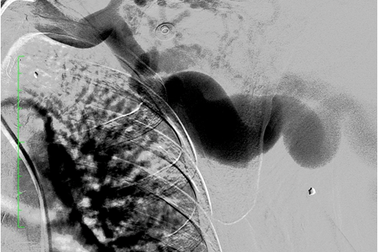

Nặng ngực, khó thở, phát hiện mảnh đạn nằm trong tim 45 nămNhập viện trong tình trạng mệt khi gắng sức, khó thở, nặng ngực... bệnh nhân được bác sĩ kiểm tra và phát hiện một mảnh đạn ghim trong nhĩ trái nằm sát đường đi của động mạch vành phải. Bệnh nhân được bác sĩ thực hiện nội soi, gắp dị vật thành công.